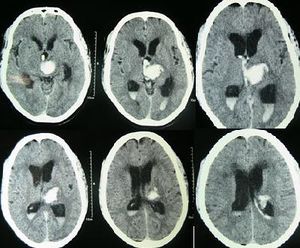

التشخيص

يعتمد التشخيص على التاريخ المرضي والفحص السريري، ومعرفة الحالة المصاحبة، بالإضافة إلى بعض الفحوصات الإشعاعية مثل :

- الأشعة المقطعية : وتعطي صور واضحة عن الحالة ومكان الانسداد.